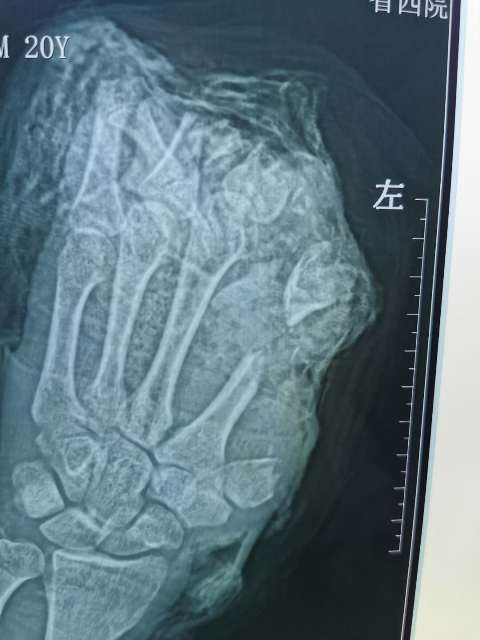

10月6日,20岁的小伙在工厂干活时左手不慎被切割机致左手拇指、示、中、环指完全离断;左小指开放伤伴肌腱神经血管离断;大鱼际皮肤软组织、环指中末节部分缺损、第一掌骨、第二掌骨部分缺损,鲜血直流。被工友慕名紧急送往我院骨二科进行救治。

病人来院时,是晚上6时,正是大家吃晚饭的时间,骨二科(显微手外科)李会晓副主任和庞仲辉副主任顾不上这些。鉴于病人的情况危重,马上安排当班医生徐文龙和瞿超医生、立即启动应急救治预案,开通急救绿色通道,组织科室人员做术前讨论制定手术首选方案及备选方案,同时积极术前准备。“手术室、麻醉师马上准备,晚7时,一切准备妥当,手术正式开始”,患者紧急送入手术室。手术由骨二科副主任医师李会晓以及庞仲辉副主任医师主刀,在当班医生徐文龙、瞿超医生、麻醉师、手术室护士等医护员人员的通力协作下,为患者实施紧急手术。由于断指手术涉及到骨骼、肌腱、血管、神经的重建,手术难度大,特别是在显微镜下吻合细如发丝的血管(0.2mm-1mm),手术过程中不能有半毫米的偏差。

经过骨二科和手术室医务人员历时10小时,彻底清除污染失活组织及伤口内大量铁屑异物、逐步固定指骨、缝合肌腱,显微下再次清创后吻合离断神经;术中见离断动脉大部分挫伤严重无法吻合就近利用手背侧静脉,移植搭桥吻合缺损动脉完成4指离断一期急诊再植,术后经补液输血,支持,抗感染,抗凝,抗痉挛,扩血管等“三抗一扩”对症治疗。目前患者再植指体成活良好,已经基本度过危险期,保住了患者的四个手指。